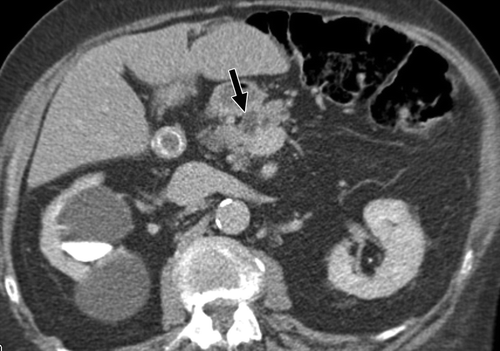

Fig. 3

Fig. 3 —84-year-old white woman. Transverse image from IV contrast-enhanced CT scan shows 3-mm cyst (arrow) in neck of pancreas.